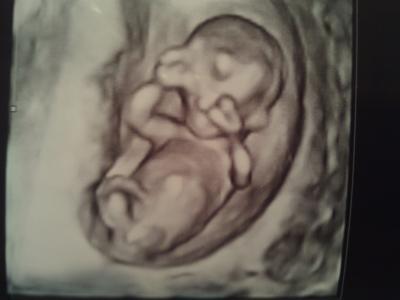

Alles in bester Ordnung!!! Nackenfalte liegt bei 1,4cm, Nasenrücken ist auch vorhanden und da "Es" sich so kräftig bewegt hat und mit den Beinen gestrampelt hat- schließt sie ein Neuralrohrdefekt aus! Dann hat meine Ärztin endlich mit 4 D geschallt ..... Ich habe Sie gefragt, ob man zwischen den Beinchen schon etwas sehen könnte.... Sie meinte eigentlich nicht.... Beim Verabschieden meinte die Ärtzin dann, in 3 Wochen lass ich mich hinreißen Ihnen zu sagen, dass es ein Junge wird Ich war auch der Überzeugung etwas im 4 D eindeutig gesehen zu haben und ich finde, man sieht es auch auf dem Bild..... Laut Ultraschall bin ich nun auch schon fast 14. Woche- beim nächsten Mal wird es dann eventuell korrigiert...... an alle die heute auch einen Termin haben, ich drück euch die Daumen und erwarte positive Berichte.... So, und hier das Bild vom kleinen Fussballer

Bild zu Wieder da vom Arzt......... schaut mal...... - Forum für August - Mamis